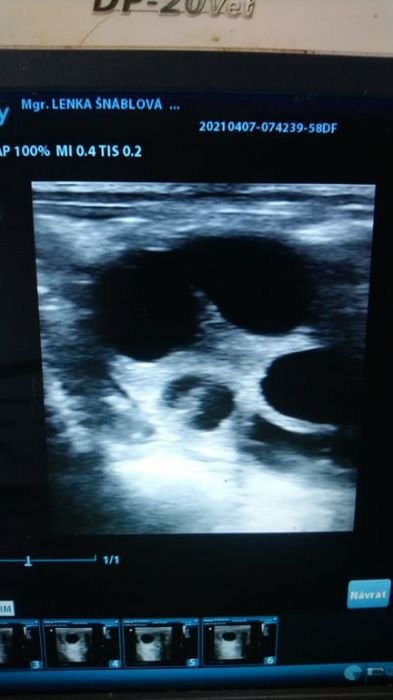

Folikulární vlna na vaječníku klisny

Chovná klisna by měla být pravidelně očkována dle vakcinačního schématu, aby se snížilo riziko případného abortu. Před připouštěním je třeba brát v potaz i roční období. V zimě je valná většina klisen v anestru, tedy v období, kdy na vaječnících nedozrávají folikuly, klisna necykluje. V jarním přechodném období začínají klisny cyklovat (únor/ březen), zpočátku folikuly atretizují – neovulují. Pro chov je také důležité zvážit, zda narozenému hříběti budou poskytnuty veškeré podmínky pro správný vývoj – kvalitní výživa, dostatek prostoru k pohybu, sociální kontakt s vrstevníky.